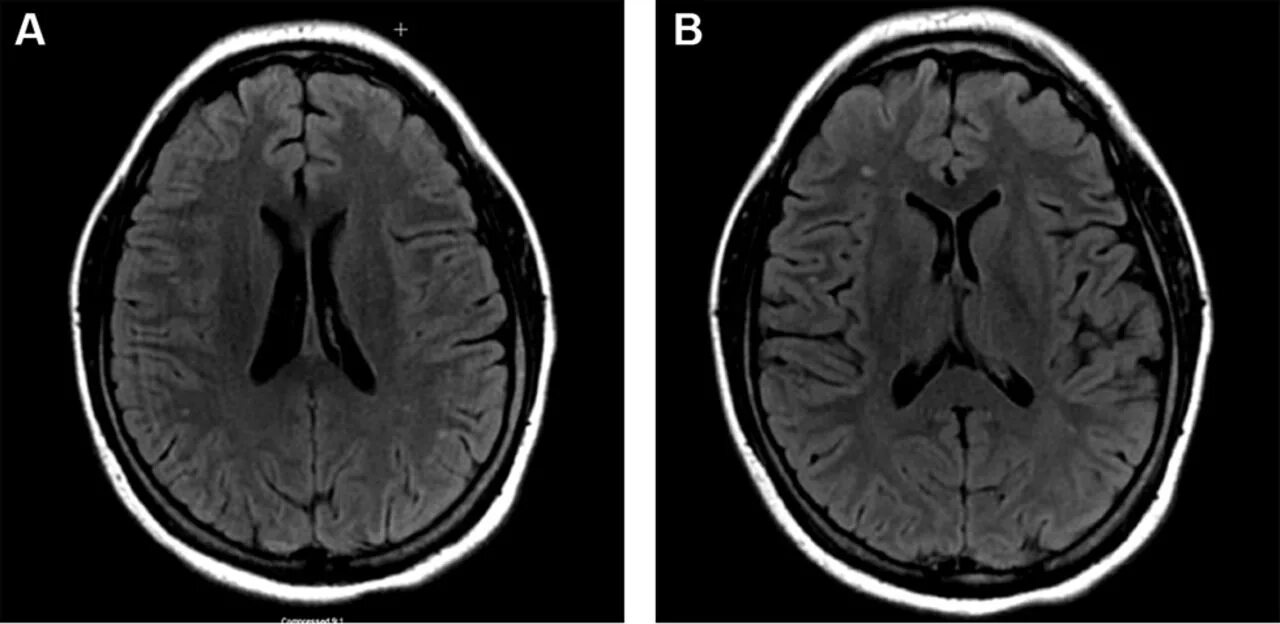

Диффузные изменения головного мозга